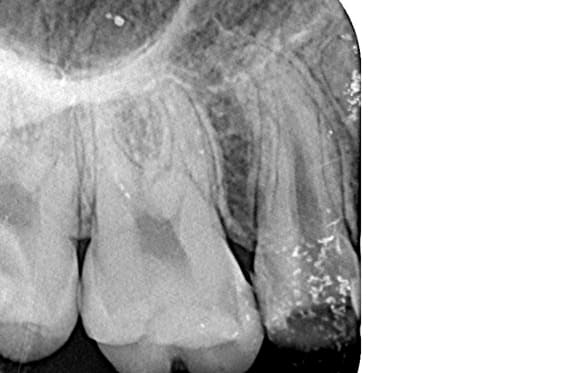

● 症例2

01 右上の頬側根に手用ファイルの破折

02 ファイル除去時

※若干の打診痛あり

03 最終の根充剤を充填